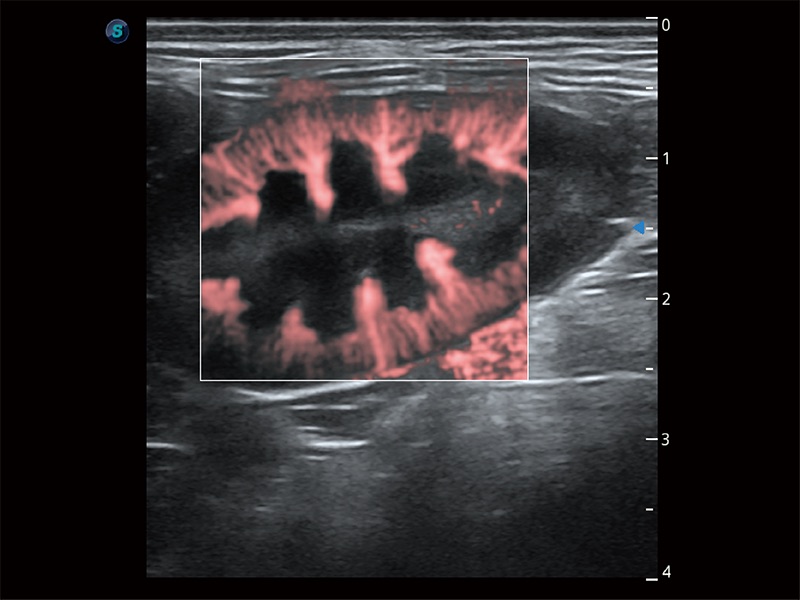

• Micro F 显微血流成像

极大提升超低速微细血流的检出能力,同时更精准地滤除软组织和超声信号,为兽用医生提供以往无法通过常规血流获得的疾病诊断信息。

• Bright Flow 立体血流成像

在传统二维血流成像的基础上,呈现血流的立体感,具有动感的生命力之美。即便是微小的血管也能轻松应对,提高了血流的视觉敏感性。

(犬)肾脏显微血流